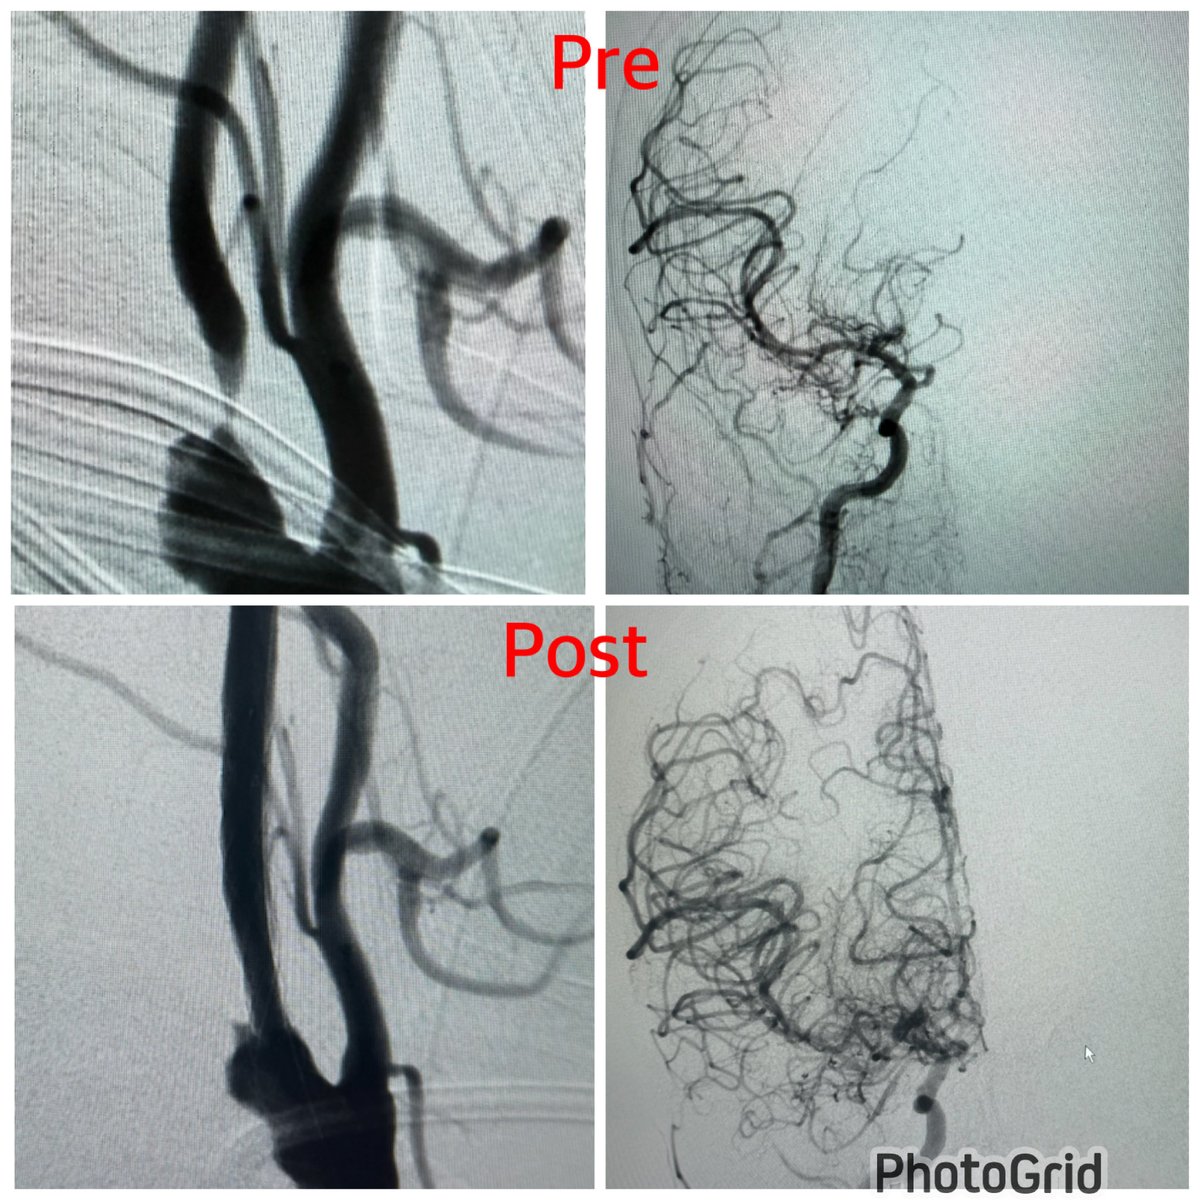

Young patient with Large complex facial AVM , complaining of tinnitus On examination feel the thrill on Rt cheek DSA showed large fistula component with large indranidal aneurysm via facial artery -superior thyroid and lingual contributing more into nidus. - Decision was made to close the high flow shunt including the aneurysm via facial artery using pressure cooker technique. Other feeder to be done in another session. Successful embo , patient doing fine and no more tinnitus or thril 🙏